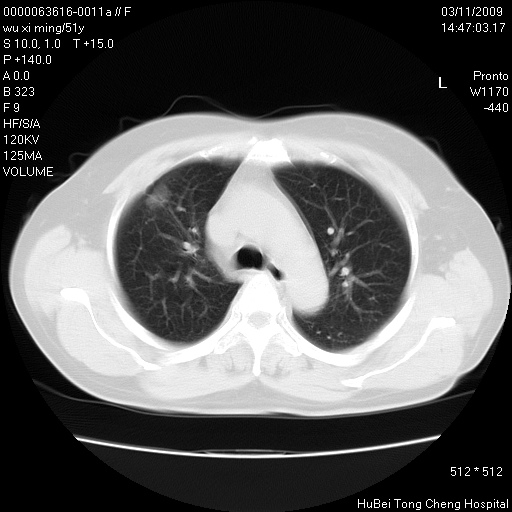

患者 女,51岁。因“胆囊炎,胆囊结石”,行常规术前胸部x线检查发现:右上肺结节病灶,建议行进一步检查。患者无咳嗽、咳痰及咯血等呼吸道症状,近期出现背部疼痛不适。

胸部ct轴位平扫(层厚10mm,螺距1.5,重建间隔10mm;部分层面:层厚3mm,螺距1.0,重建间隔3mm),图像如下:

1、周围型肺癌。(毛刺正、血管束集征,分叶。)

集束征,胸膜牽拉征,毛刺,淺分葉高度提示ca.

右肺周围型肺癌伴肺内转移及胸椎转移。已无手术机会。